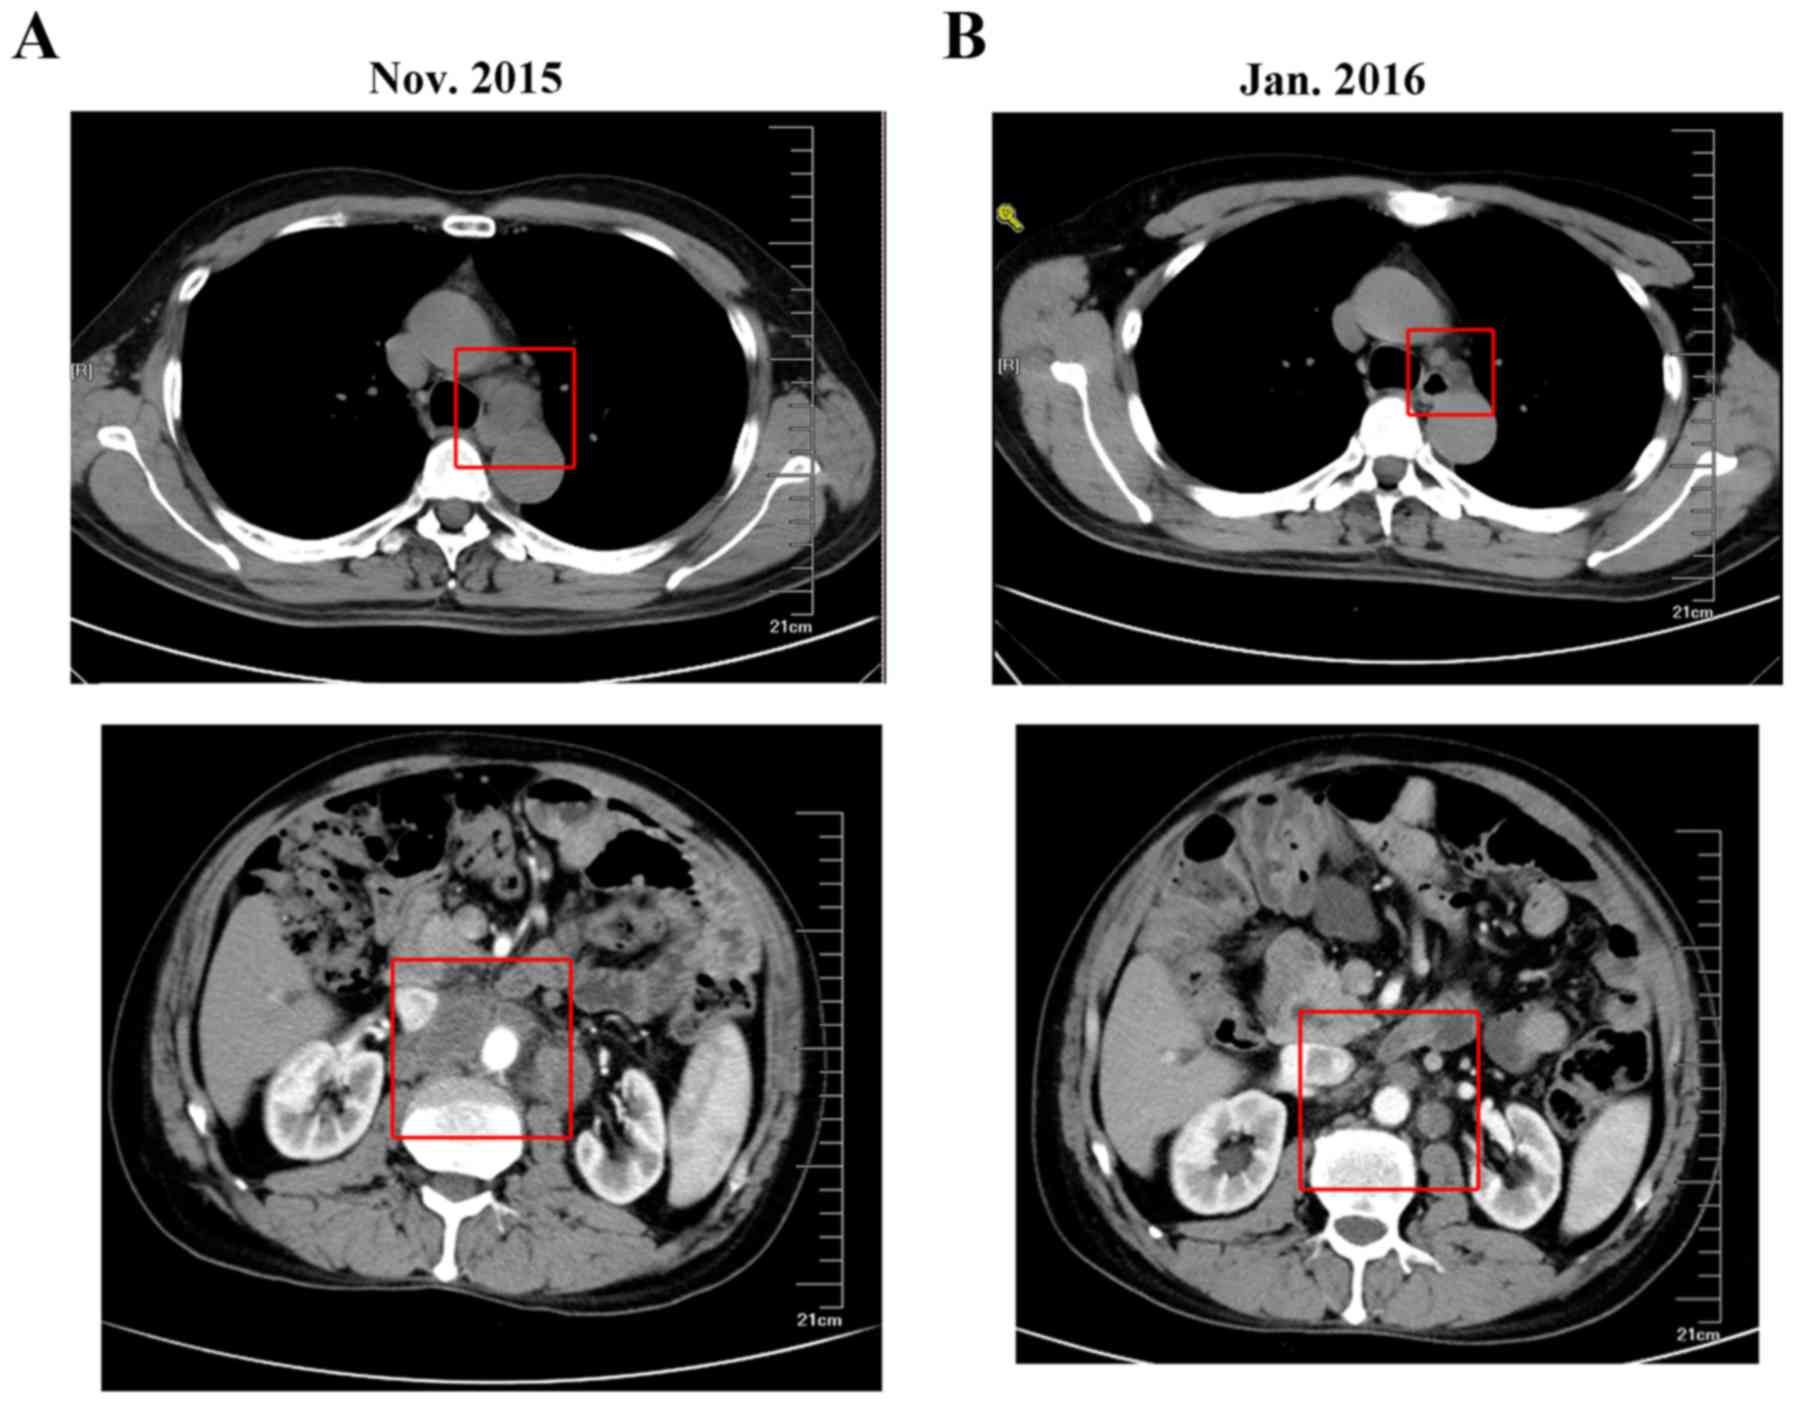

In November 2015, the patient returned and was reexamined. At this time, CT examination revealed mediastinal and retro-peritoneal lymphadenectasis, which indicated disease progression. Considering the benefit from the use of trastuzumab in first-line chemotherapy (disease control was maintained for 26 months), a second-line regimen of 6 cycles of paclitaxel liposome (L-PTX, 175 mg/m2 on day 1) and S-1 (50 mg twice daily on days 1–14) together with trastuzumab (8 mg/kg first dose and 6 mg/kg followed on day 0) was selected. A CT scan in January 2016 revealed that the mediastinal and retro-peritoneal lymphadenectasis had decreased in size (Fig. 3). Furthermore, the tumor marker levels from the serum sample (carcinoembryonic antigen and cancer antigen) were markedly decreased (Fig. 4). In March 2016, 10-MV radiotherapy (tumor absorption dose 50 Gy/25 fraction) targeting abdominal lymph node lesions was performed. Between March 2016 and August 2016, maintenance treatment of trastuzumab combined with S-1 was administered. The disease was kept stable and the tumor markers exhibited little fluctuation until a new pulmonary nodule was observed during a CT scan in August 2016. In the subsequent 5 months, the targeted drug was changed to apatinib (250 mg twice daily, from August 2016 to December 2016) due to newly observed pulmonary lesions. In December 2016, a further CT scan revealed disease progression resulting from the pulmonary lesions (Fig. 5).

Figure 3.

CT scans comparing the mediastinal/retroperitoneal lymphadenectasis prior to and following the second-line chemotherapy regimen combined with trastuzumab. (A) CT in November 2015 revealed mediastinal (upper) and retroperitoneal (lower) lymphadenectasis. (B) CT in January 2016 demonstrated that the mediastinal (upper) and retroperitoneal (lower) lymphadenectasis was reduced in size following second-line chemotherapy combined with trastuzumab. CT, computed tomography.